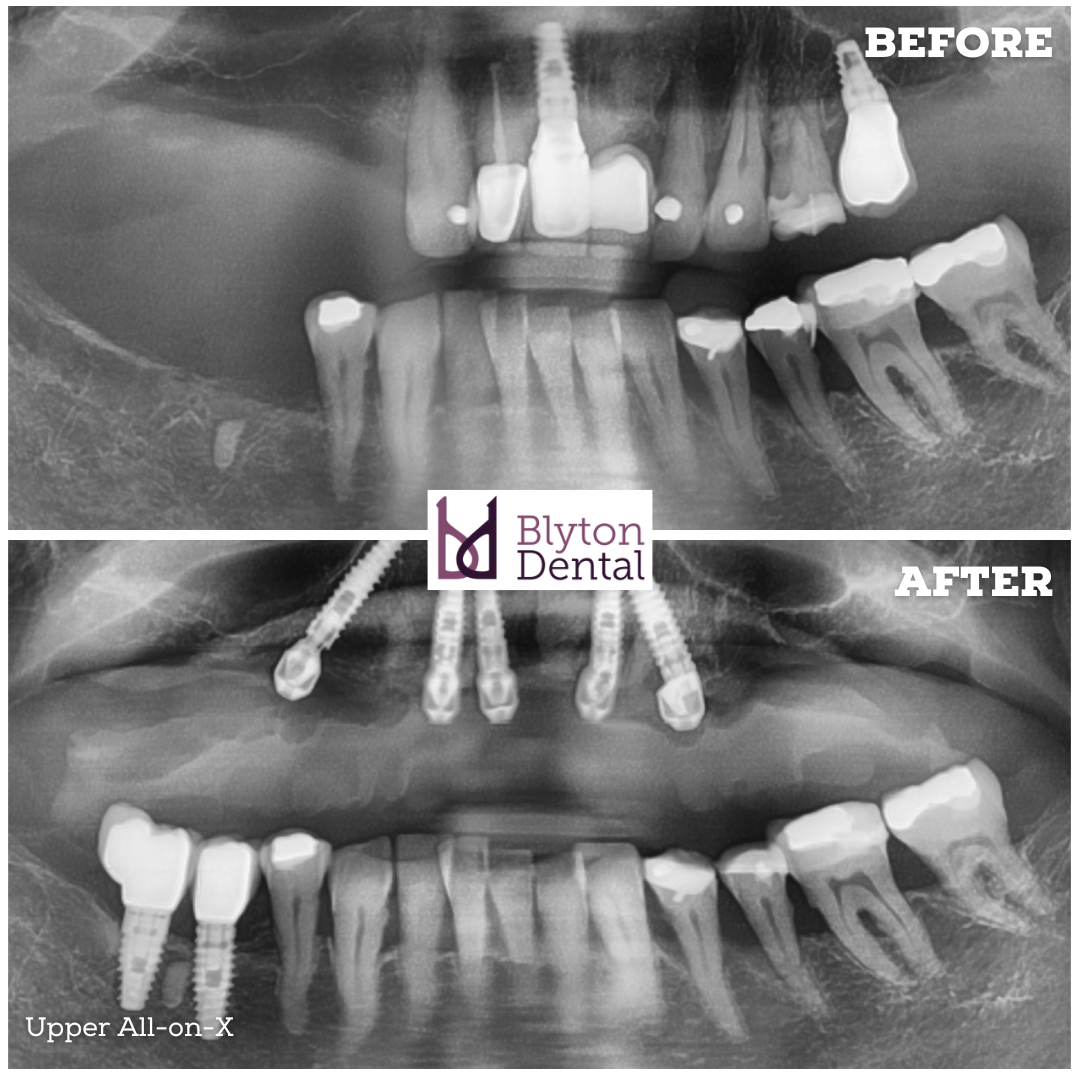

This patient presented with a failing implant and missing teeth.

After removing the failed implant, we were able to retain one well-integrated implant...

And place 4 additional implants to support a fixed All-on-X upper bridge.

The missing teeth on the lower right were replaced with individual implant crowns.